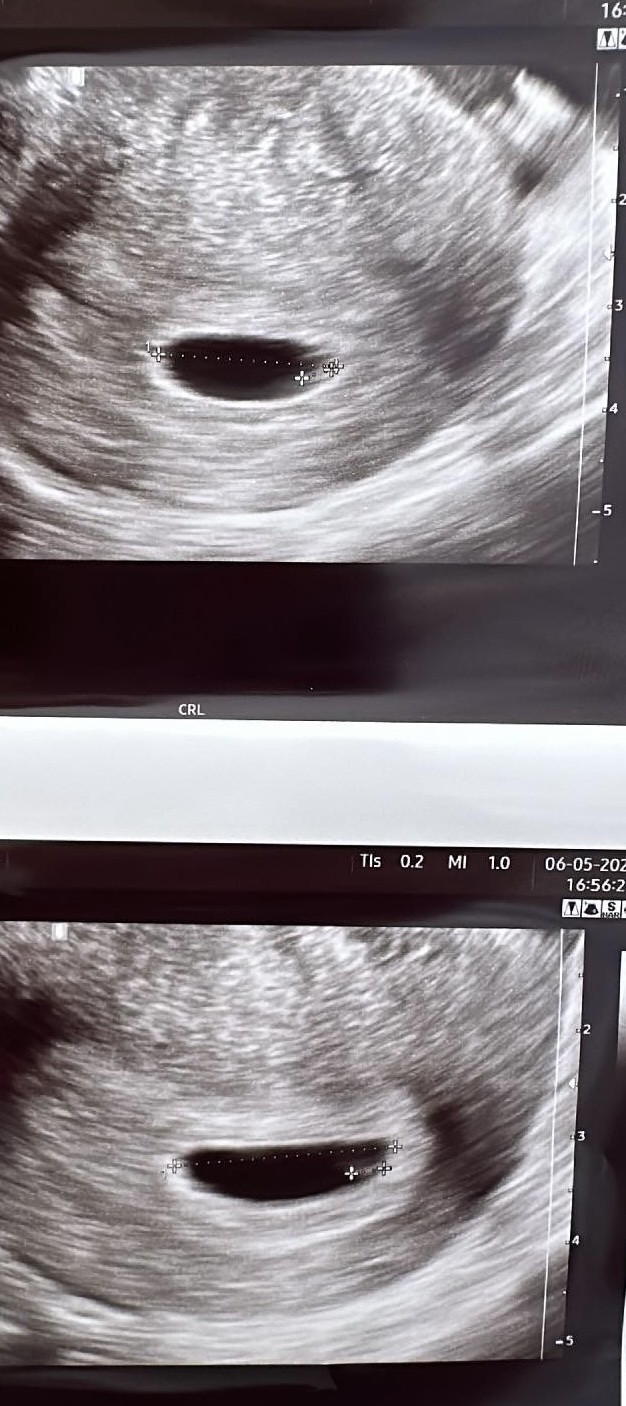

Witam, lekarz ocenił ciążę na 5 tygodni 5 dni. Czy waszym zdaniem wszystko jak na tym etapie jest prawidłowo? Następną wizytę mam za 3 tygodnie, serduszka nie było jeszcze słychać i lekarz nie mówił że mam się czymś martwić, no ale ja już tak mam, nie znam się i nic tam na tym zdjęciu nie widzę 😏 proszę bez hejtu, ja po prostu jestem panikarą

Ja myślę, że do serca to jeszcze trochę bo tutaj nawet zarodka nie widać. Więc te 3 tygodnie na kolejną wizytę to jak najbardziej ok. A ile mm ma pęcherzyk?